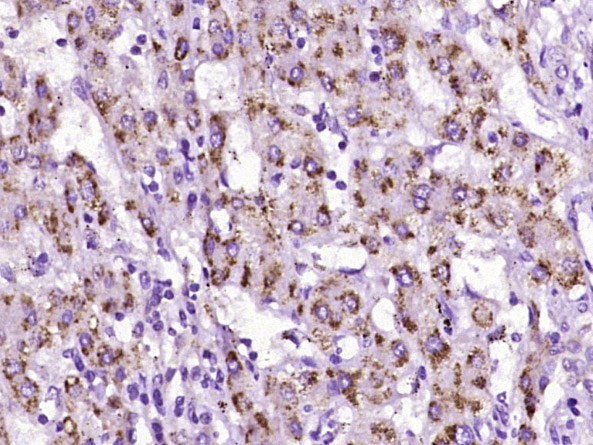

Paraformaldehyde-fixed, paraffin embedded (human gastric carcinoma); Antigen retrieval by boiling in sodium citrate buffer (pH6.0) for 15min; Block endogenous peroxidase by 3% hydrogen peroxide for 20 minutes; Blocking buffer (normal goat serum) at 37°C for 30min; Antibody incubation with (TYPH) Polyclonal Antibody, Unconjugated (bs-3809R) at 1:400 overnight at 4°C, followed by operating according to SP Kit(Rabbit) (sp-0023) instructionsand DAB staining.

Paraformaldehyde-fixed, paraffin embedded (human liver carcinoma); Antigen retrieval by boiling in sodium citrate buffer (pH6.0) for 15min; Block endogenous peroxidase by 3% hydrogen peroxide for 20 minutes; Blocking buffer (normal goat serum) at 37°C for 30min; Antibody incubation with (TYPH) Polyclonal Antibody, Unconjugated (bs-3809R) at 1:400 overnight at 4°C, followed by operating according to SP Kit(Rabbit) (sp-0023) instructionsand DAB staining.